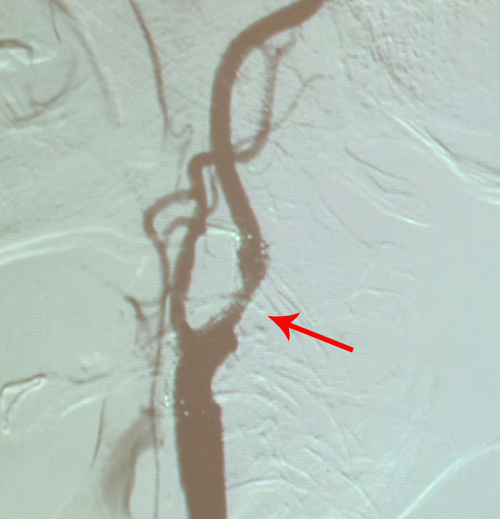

术中取出的斑块

患者中老年男性,动脉粥样硬化性危险因素较多,累及冠脉、颈动脉及双下肢动脉,病变程度较重,但患者目前无TIA 及脑卒中症状。右颈内动脉狭窄尚未达70%,但斑块内溃疡,属不稳定斑块,且狭窄已>50%,产生同侧脑卒中风险较大,因此有进一步治疗指征。因对于溃疡斑块,CAS疗效不如CEA,因此CEA相对适合。患者合并有冠脉三支病变,预防围手术期心肌梗塞是关键。

2010年12月6日,协作组张勤奕教授和王冬青教授在西安交大第一医院为其顺利实施右侧颈内动脉内膜剥脱术。